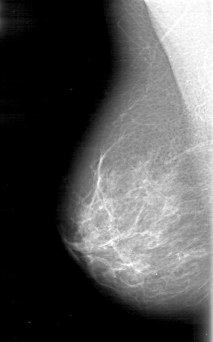

D_4054_1.RIGHT_MLO

RIGHT_CC LINES 5206 PIXELS_PER_LINE 3301 BITS_PER_PIXEL 12 RESOLUTION 43.5 NON_OVERLAY

RIGHT_MLO LINES 5116 PIXELS_PER_LINE 3181 BITS_PER_PIXEL 12 RESOLUTION 43.5 NON_OVERLAY